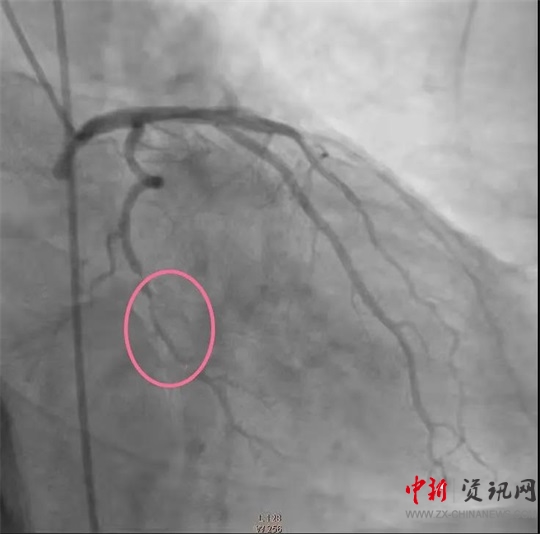

經(jīng)過一系列的術(shù)前準(zhǔn)備并經(jīng)患者家屬同意后,立即繞行病房進(jìn)入介入手術(shù)室,實(shí)施緊急手術(shù)。卒中中心團(tuán)隊(duì)、胸痛中心團(tuán)隊(duì)和介入團(tuán)隊(duì)密切配合,為患者分別實(shí)施了腦動脈造影+主動脈弓造影+顱內(nèi)動脈瘤栓塞術(shù)+冠狀動脈造影術(shù)+經(jīng)皮冠狀動脈支架植入術(shù),成功把患者從死亡邊緣拉回。目前,患者病情穩(wěn)定,各項(xiàng)指標(biāo)良好。

(冠脈支架植入前)

(冠脈支架植入后)